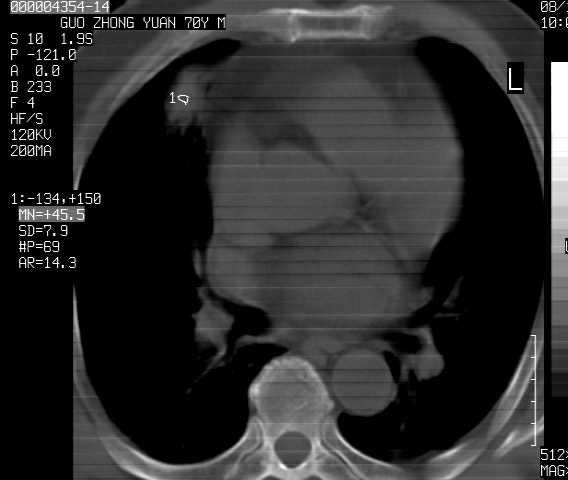

以下是引用sdzyy在2008-12-1 11:49:00的发言:[br]图像不全,请上传,右下肺炎症可能性大,占位待排.

以下是引用zjzjr在2008-12-1 14:53:00的发言:[br]图像不全,请上传,右下肺炎症可能性大,占位待排.心影增大,建议进一步检查.